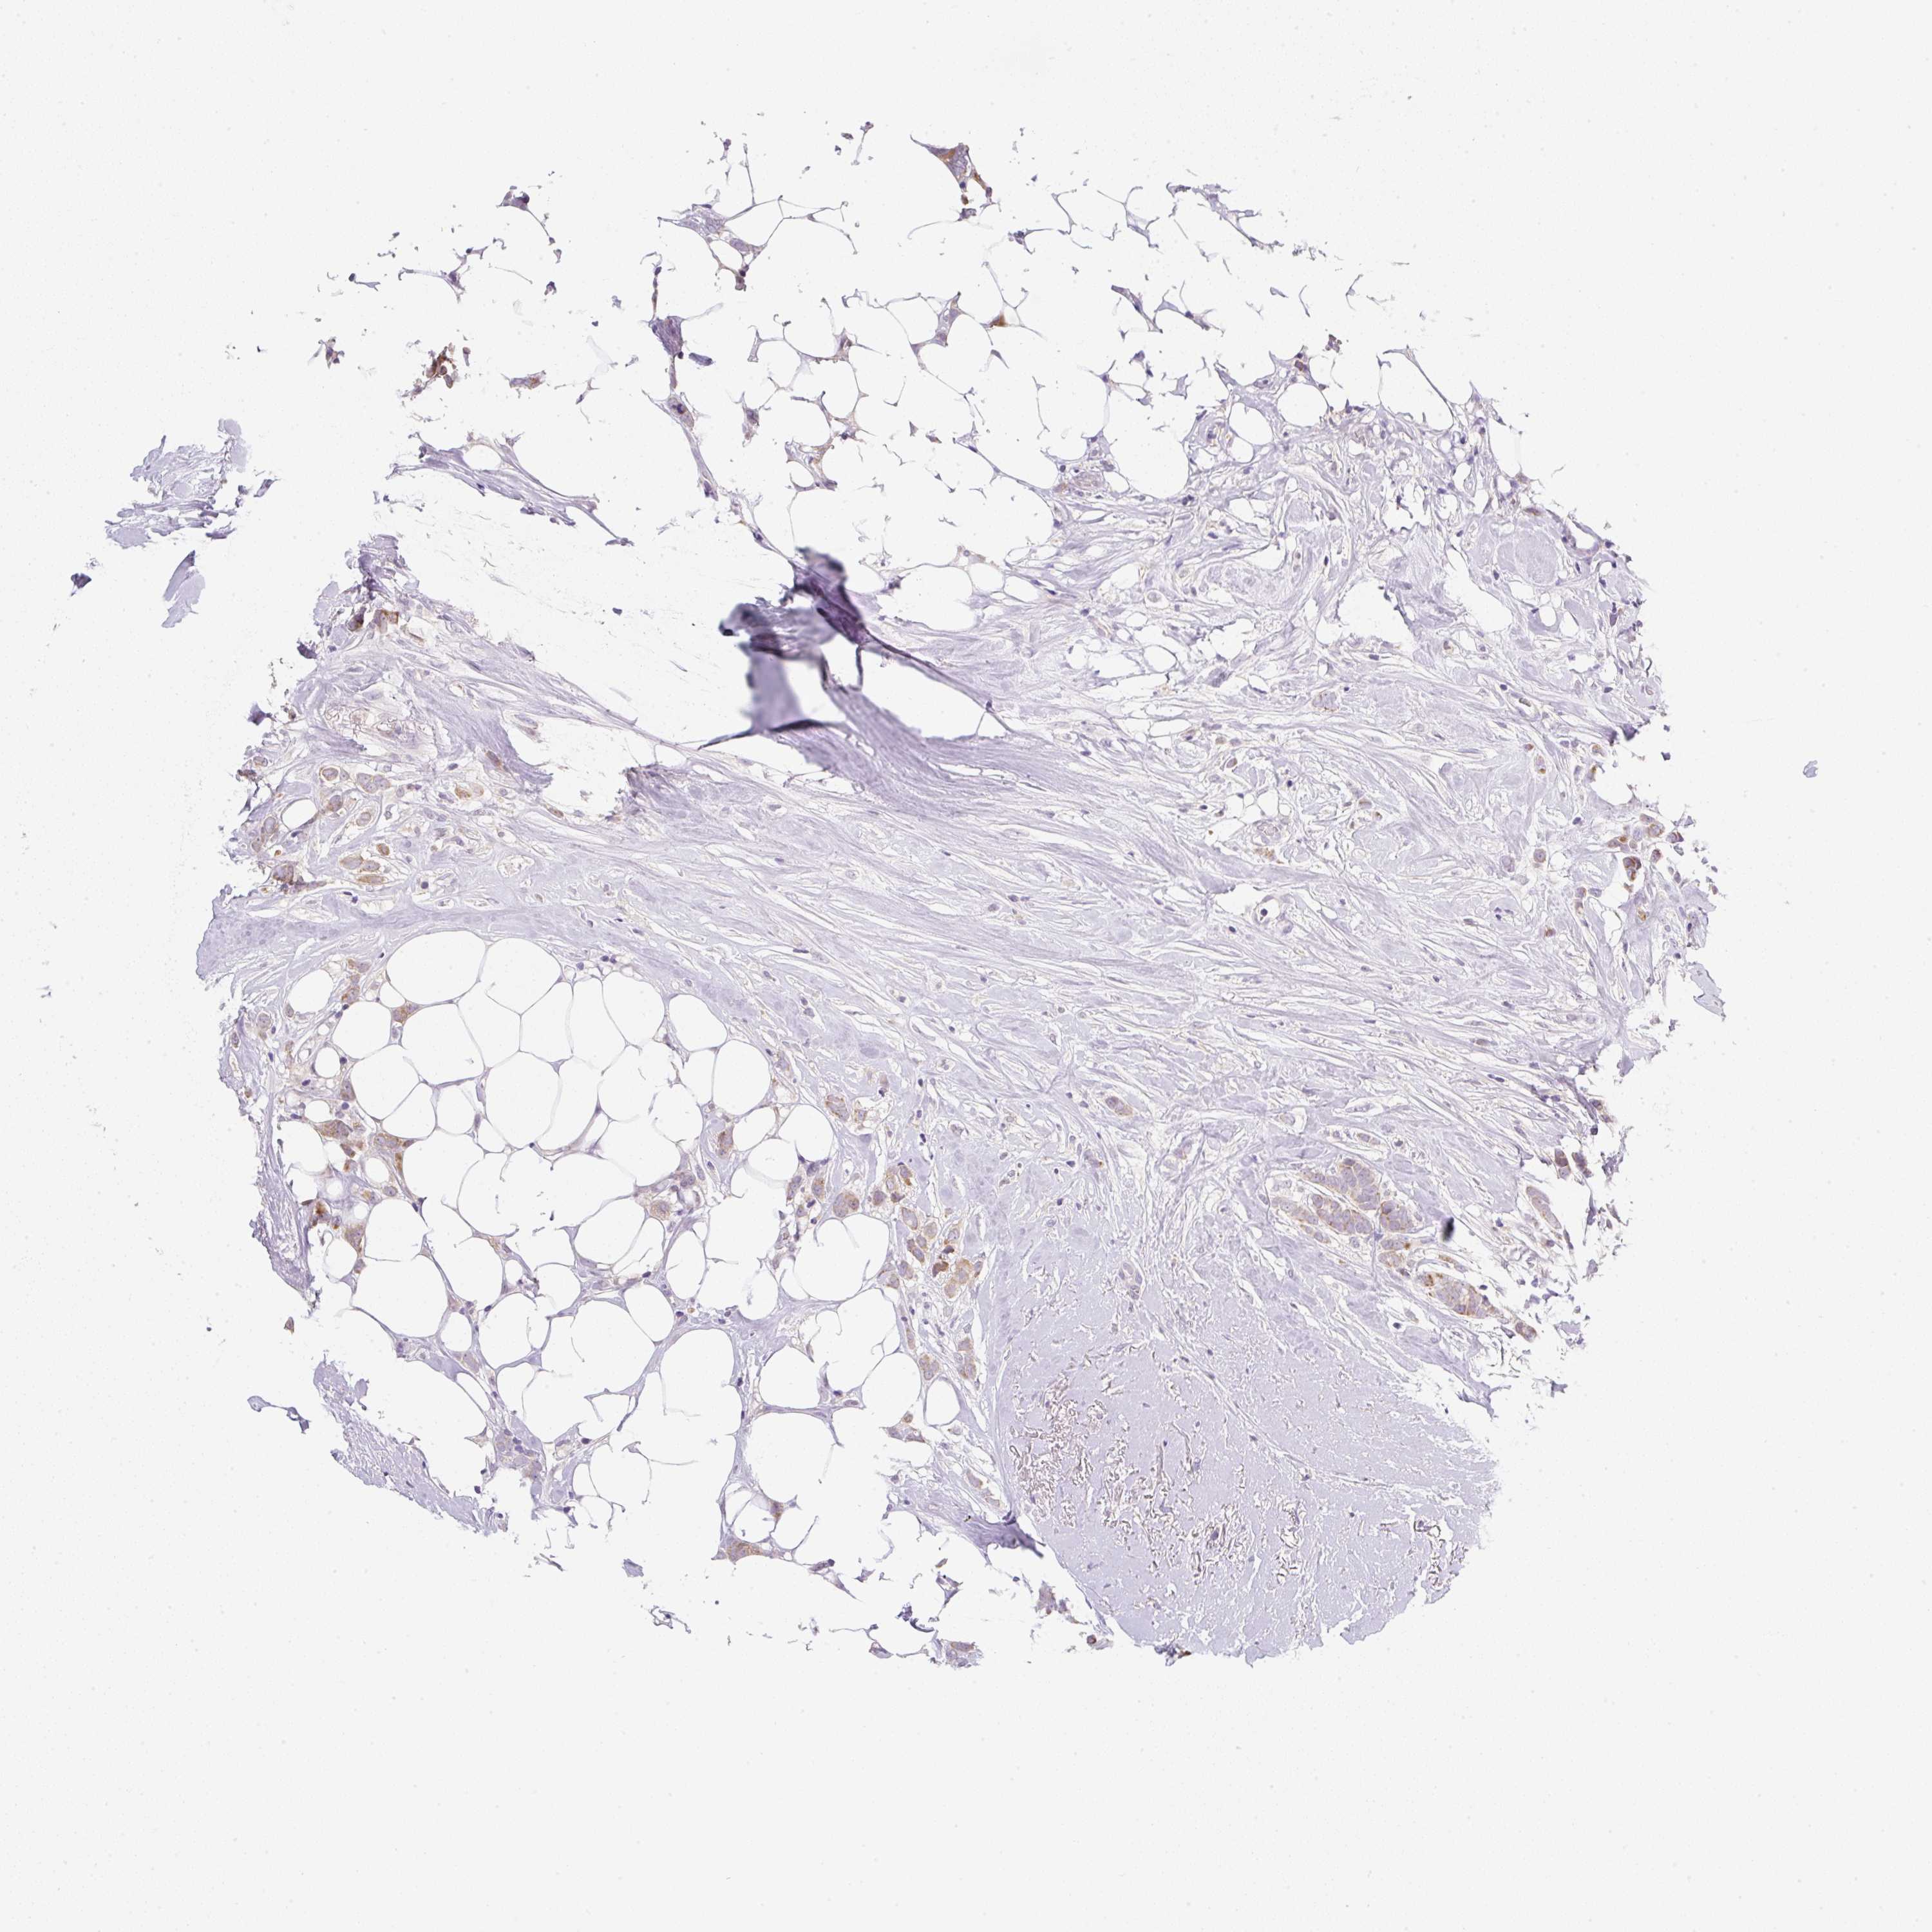

CANCER BREAST CANCER Show tissue menu

BRCA TCGA BRCA VALIDATION PROTEIN EXPRESSION